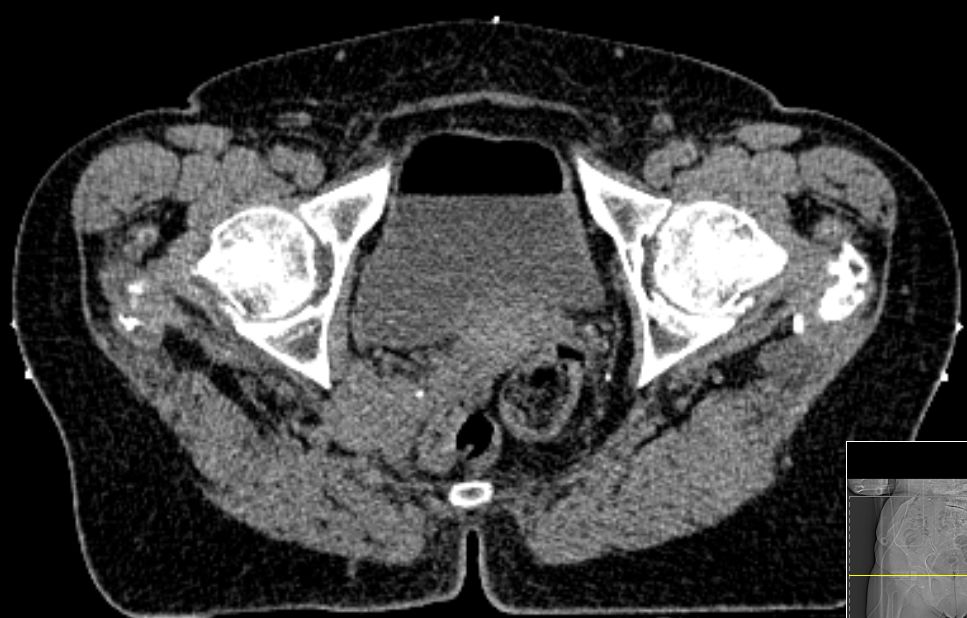

64jährige Frau, die 1 Jahr nach Melanommetastasen der linken Leiste

einen vergrößerten Lymphknoten lateral der A. iliaca externa links entwickelte.